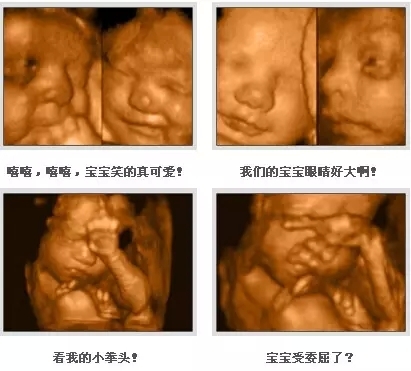

四维彩超能够全方位、多角度的观察宫内胎儿的生长发育情况,如胎儿孕周、大小,还可排查胎儿先天畸形疾病。如唇腭裂、无脑儿、脑脊膜膨出、脐部肠膨出、肠道闭锁、尿道梗阻、短肢畸形、四心腔、羊水过多、过少等。四维彩超对于优生极其关键,可不少孕妈会遇到一种尴尬的情况,也让B超医生很头疼,那便是胎宝宝老趴着,基本上看不到五官及表情。